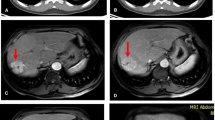

Among these 17 HCC lesions, eight (47.1%), eleven (64.7%), nine (52.9%), and seven (41.2%) positive findings were obtained on Fa, HPI, MTT, and Ki PET/CT images, respectively. Twelve (70.6%) positive findings were obtained on the total parameter images, and nine (52.9%) positive findings were detected on conventional PET/CT (P = 0.508); parameter images detected six (35.3%) HCC tumors that were negative on conventional PET/CT (Fig. 3). Using perfusion and early-uptake PET/CT, the positive rate of an HCC diagnosis was enhanced from 52.9% on conventional PET/CT to 88.2% using the combined method (P = 0.031).

Parameter images identify primary hepatocellular carcinoma (marked with arrows) with negative findings on conventional PET/CT. a Nonenhanced (NE) CT showed areas of slightly decreased opacity in the right lobe of the liver; the arterial phase (AP) of enhanced CT showed abnormal vascular enhancement, and the venous phase showed slightly heterogeneous enhancement. b Conventional PET/CT showed negative findings in the liver. c Parameter imaging showed areas of increased Fa, HPI and Ki and decreased MTT compared with that in the surrounding liver tissue